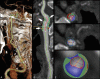

Identification of carotid artery atherosclerosis is conventionally based on measurements of luminal stenosis and surface irregularities using in vivo imaging techniques including sonography, CT and MR angiography, and digital subtraction angiography. However, histopathologic studies demonstrate considerable differences between plaques with identical degrees of stenosis and indicate that certain plaque features are associated with increased risk for ischemic events. The ability to look beyond the lumen using highly developed vessel wall imaging methods to identify plaque vulnerable to disruption has prompted an active debate as to whether a paradigm shift is needed to move away from relying on measurements of luminal stenosis for gauging the risk of ischemic injury. Further evaluation in randomized clinical trials will help to better define the exact role of plaque imaging in clinical decision-making. However, current carotid vessel wall imaging techniques can be informative. The goal of this article is to present the perspective of the ASNR Vessel Wall Imaging Study Group as it relates to the current status of arterial wall imaging in carotid artery disease.